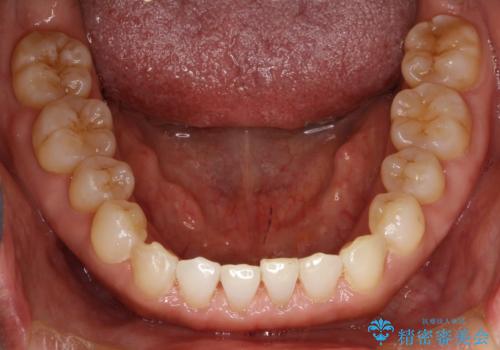

前歯の隙間 インビザラインによる目立たない成人矯正

- 前歯の隙間を気にされて来院されました。

インビザラインにて、目立たずに矯正治療を行うこととしました。

歯と歯の間にある隙間を閉じるのは、インビザラインでもしっかり治療できます。